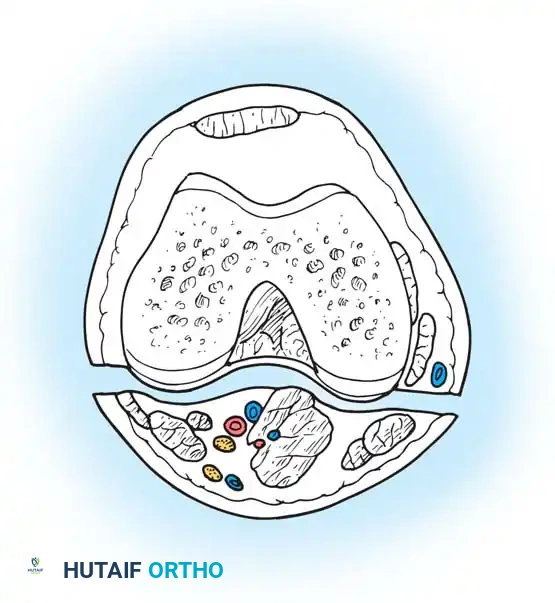

In CP, the hip and the knee are tightly coupled due to the complex network of "two-joint muscles" that cross both articulations. These crucial structures include the rectus femoris anteriorly, the gracilis medially, and the semimembranosus, semitendinosus, and biceps femoris posteriorly. Pathological conditions affecting these muscles—whether dynamic spasticity or fixed myostatic contracture—profoundly alter the kinematics of both joints. A similar interdependent relationship exists between the knee and the ankle via the gastrocnemius muscle.

Hamstring strength, spasticity, and knee contractures are assessed with the patient in both prone and supine positions.

Prone Assessment: The examiner extends the hips maximally and exerts gentle downward pressure on the calves. The angle formed between the femur and the tibia after dynamic spasticity has been overcome represents the true degree of fixed soft-tissue contracture behind the knee.

Supine Assessment (Popliteal Angle): The examiner stabilizes the contralateral knee in maximum extension. The ipsilateral hip is flexed to 90 degrees, and the knee is passively extended. If knee extension is limited, hamstring tightness is present.

Fig. 30-20 Testing for hamstring spasticity and contracture. A, Patient is supine with hips extended. Pressure is exerted over knees, forcing them into extension. Flexion remaining in knees is absolute knee flexion contracture. B, Knee on side to be tested is flexed, while opposite knee is stabilized in extension. C, Attempted flexion of hip results in more flexion of knee.